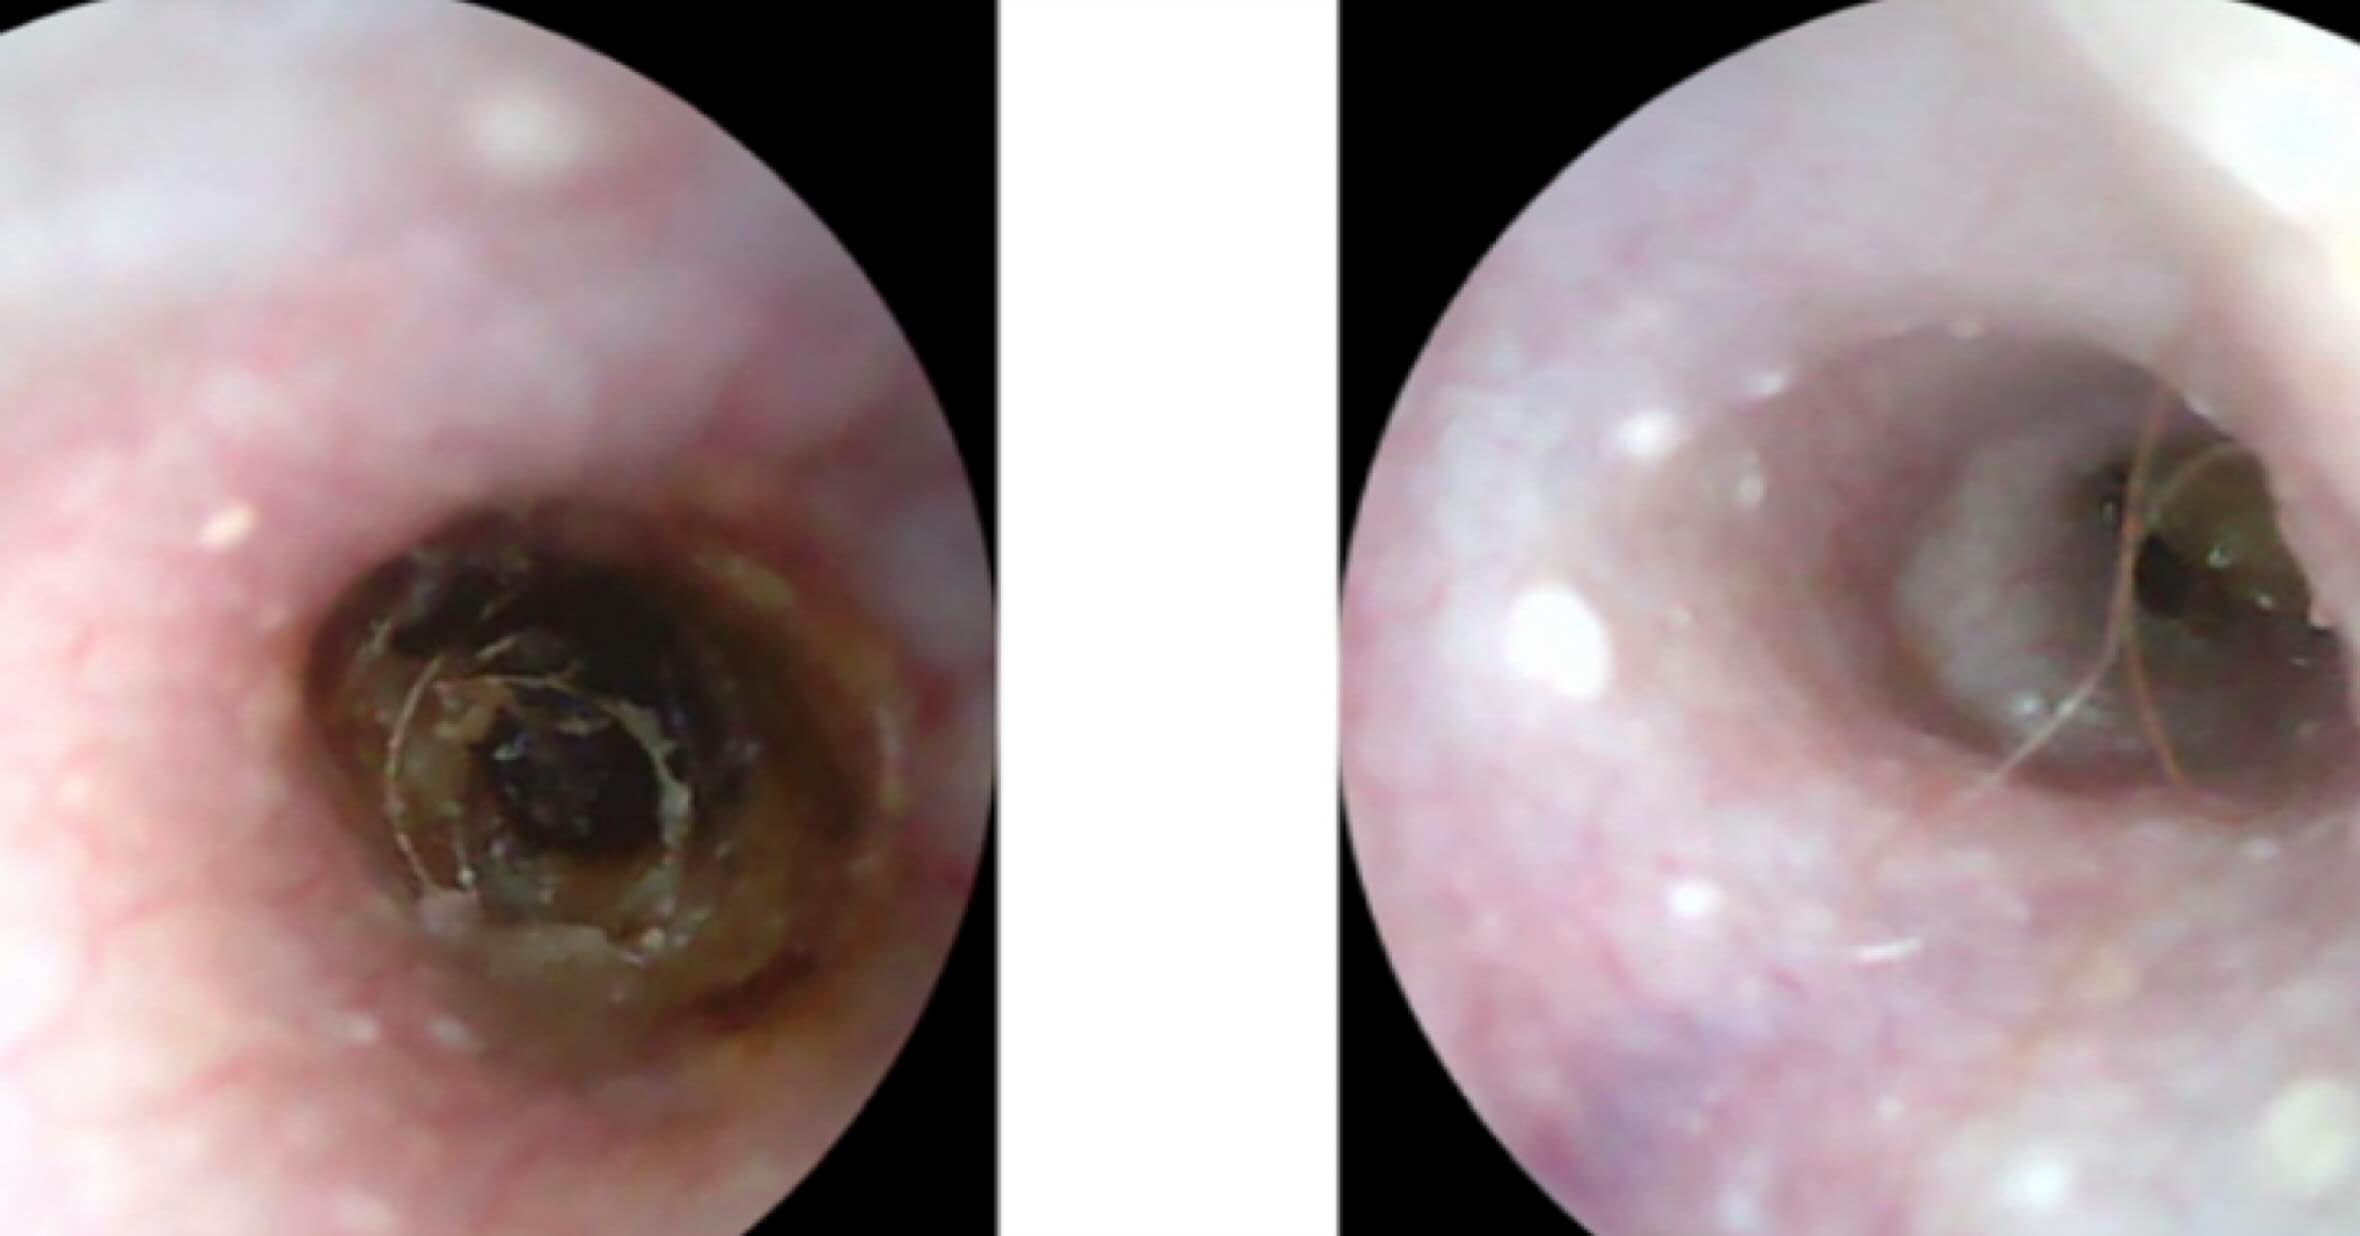

歯周疾患診療

人と同じように犬猫も口腔内環境が重要です。